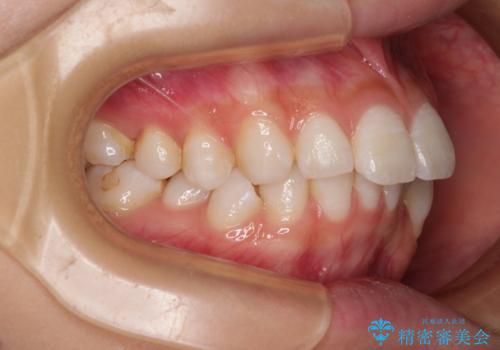

斜め前に飛び出した前歯 抜歯矯正で素敵な横顔に

- 口を閉じたときに飛び出してしまう上顎前歯を気にして来院された患者様です。

下顎はデコボコが気になっていたため、上下左右第一小臼歯4本を抜去して、ワイヤー装置にて口元の突出感を改善するよう矯正治療を行うこととしました。

下唇に前歯が当たって跡が残ってしまう状態でしたが、スッキリとした口元に仕上げることができました。